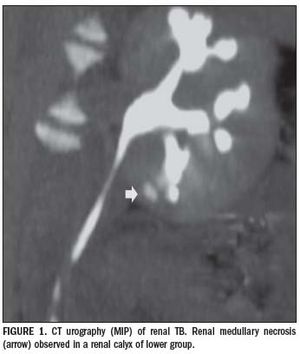

Published: January 11th 2011 | Updated: